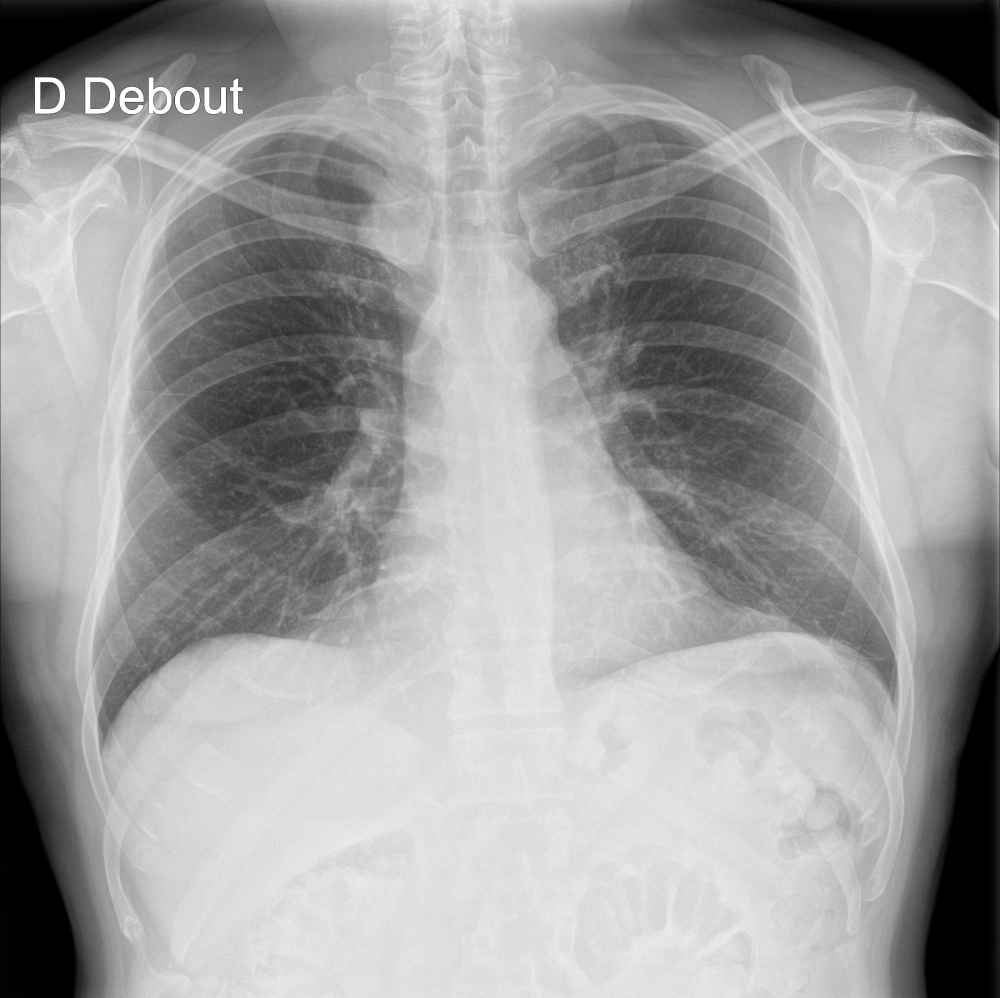

Indication

An 80-year-old male with a previously normal chest X-ray presents for CT evaluation 9 months later, which reveals findings suggestive of lung cancer.

Results

ChestView detected the mediastinal mass on the initial X-ray.